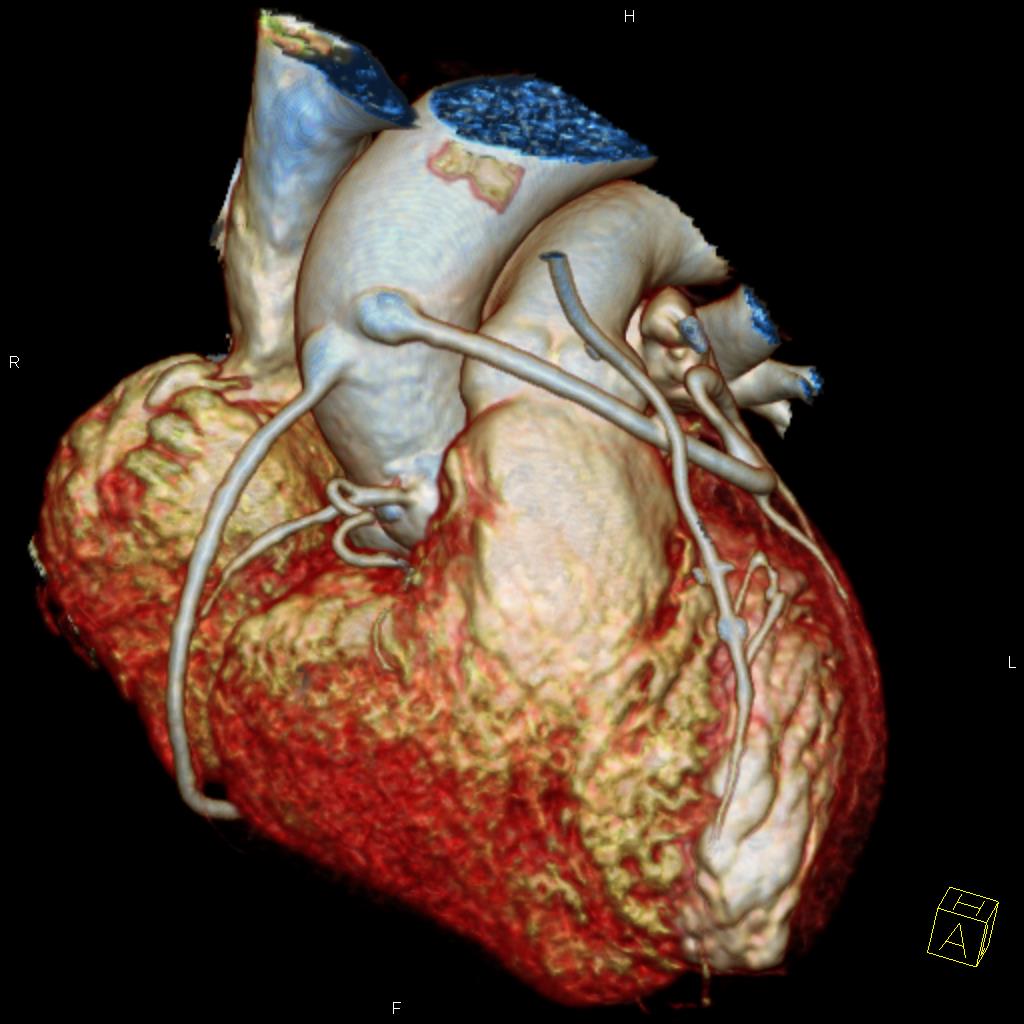

Sie hat sich als eine bedeutende Methode zur nichtinvasiven, das heisst unblutigen Darstellung der Herzkranzgefäße etabliert. Mit Hilfe der CT können bei angemessen ausgewählten und vorbereiteten Patienten mit grosser Zuverlässigkeit Aussagen über das Vorhandensein möglicher Engstellen oder Verschlüsse der Herzkranzgefässe (Abbildung 1), das Ausmass der Herzkranzgefässverkalkungen und die Anatomie des Herzens getroffen werden, und das ohne Herzkatheteruntersuchung. Sind die Herzkranzgefässe bereits erkrankt, so kann unter bestimmten Bedingungen auch eine Darstellung von Bypassgefässen (Abbildung 2) oder Stents erfolgen. Eine blutige Untersuchung mittels Herzkatheter kann somit in vielen Fällen vermieden werden (Abbildung 3). Sollten in der CT relevante Engstellen in einem oder mehreren Koronargefäßen auffallen, muss jedoch meist eine Herzkatheteruntersuchung zur weiterführenden Diagnostik und ggf. Therapie erfolgen.

Abbildung 2: Dreidimensionale Rekonstruktion eines Patienten nach Bypassoperation